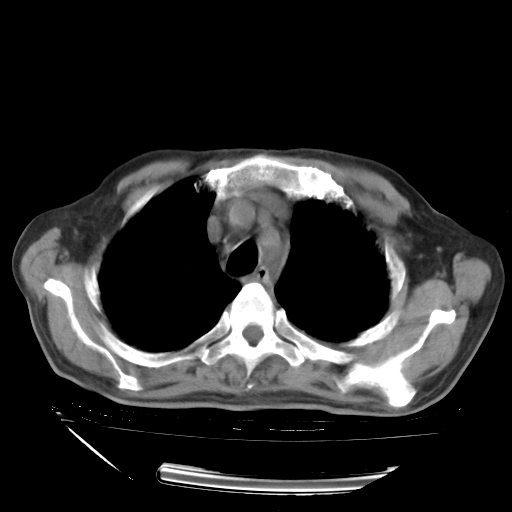

经过24天治疗,岳父的病情基本稳定。生活基本可以自理,可以下床活动。呼吸困难早已消失。体温基本正常。

只是甲强龙用80mg时血小板升到正常,改为60mg后又降到63×10*9/L。

主要治疗甲强龙80mg×14天,60mg×10天;同时抗结核(异烟肼+利福平+乙胺丁醇)。环磷酰胺0.1 tid 10天。

特别感谢胡教授、高管、桃子版主给出关键的治疗建议。桃版把所有肺部影像和全部临床资料请所在医院呼吸科、感染病科、结核科、临床免疫科专家会诊。临床免疫科专家制定了完整的治疗方案。

下一步治疗强地松+环磷酰胺+抗结核。 |